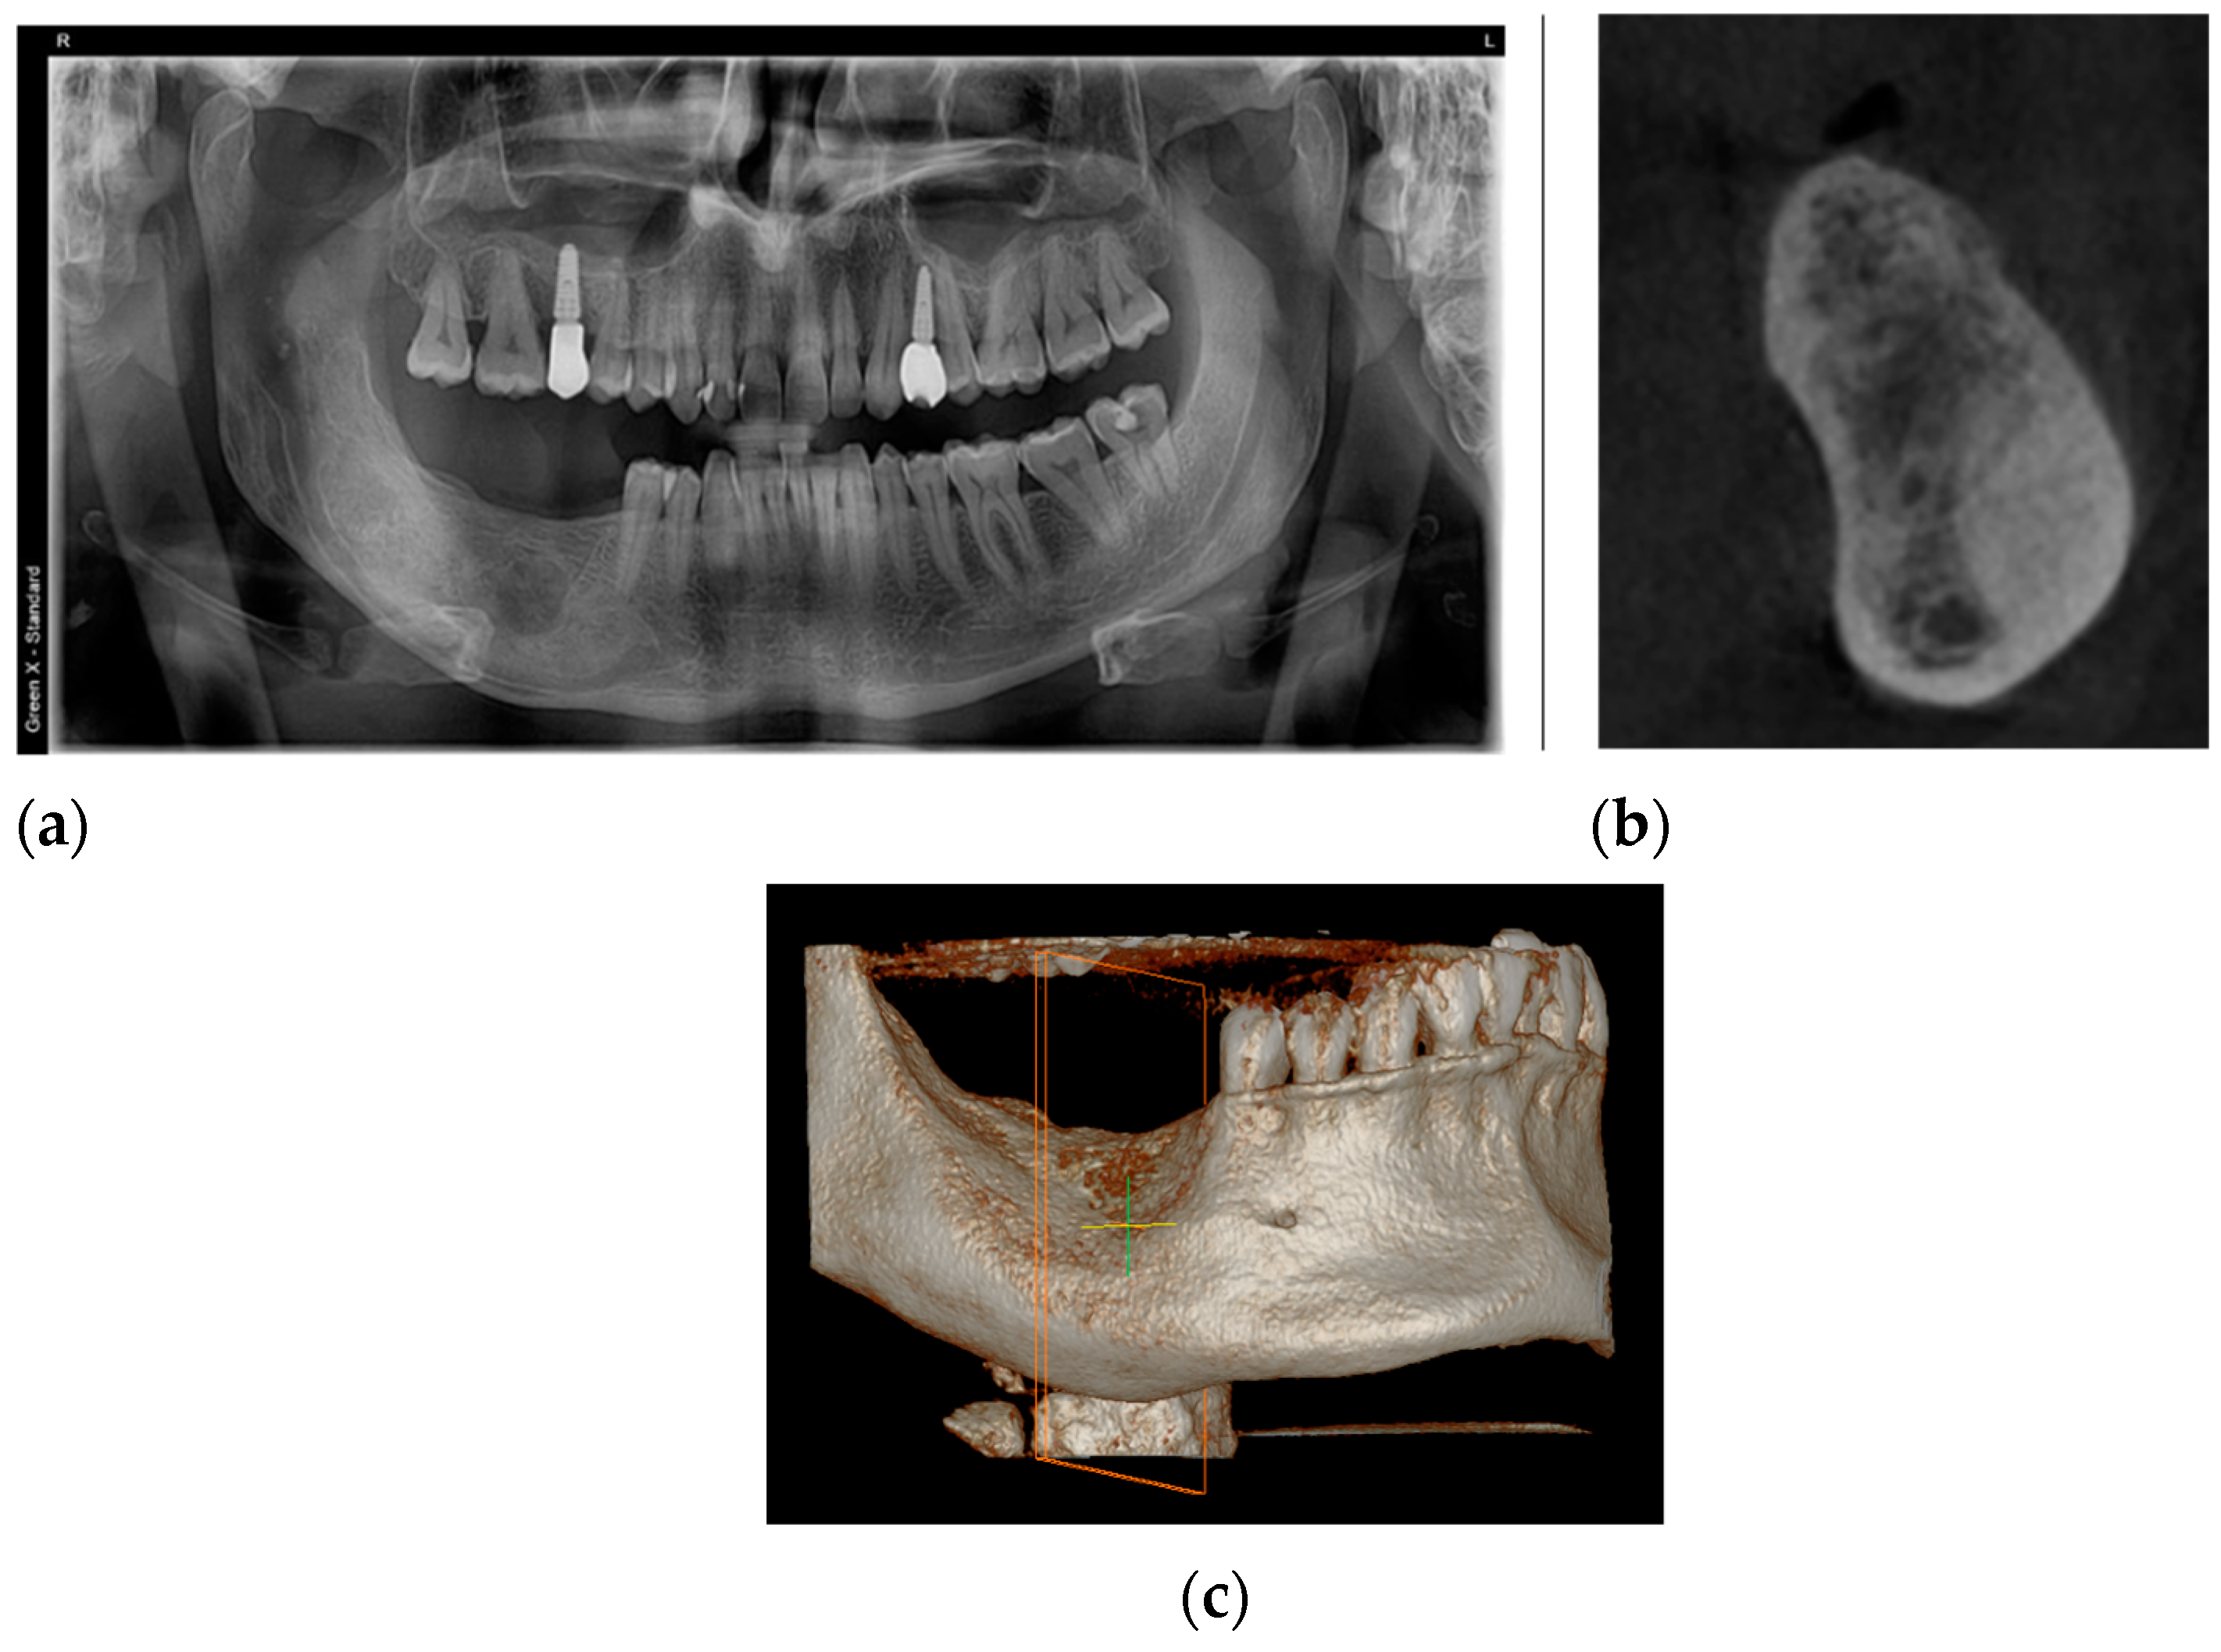

2. Case Presentation